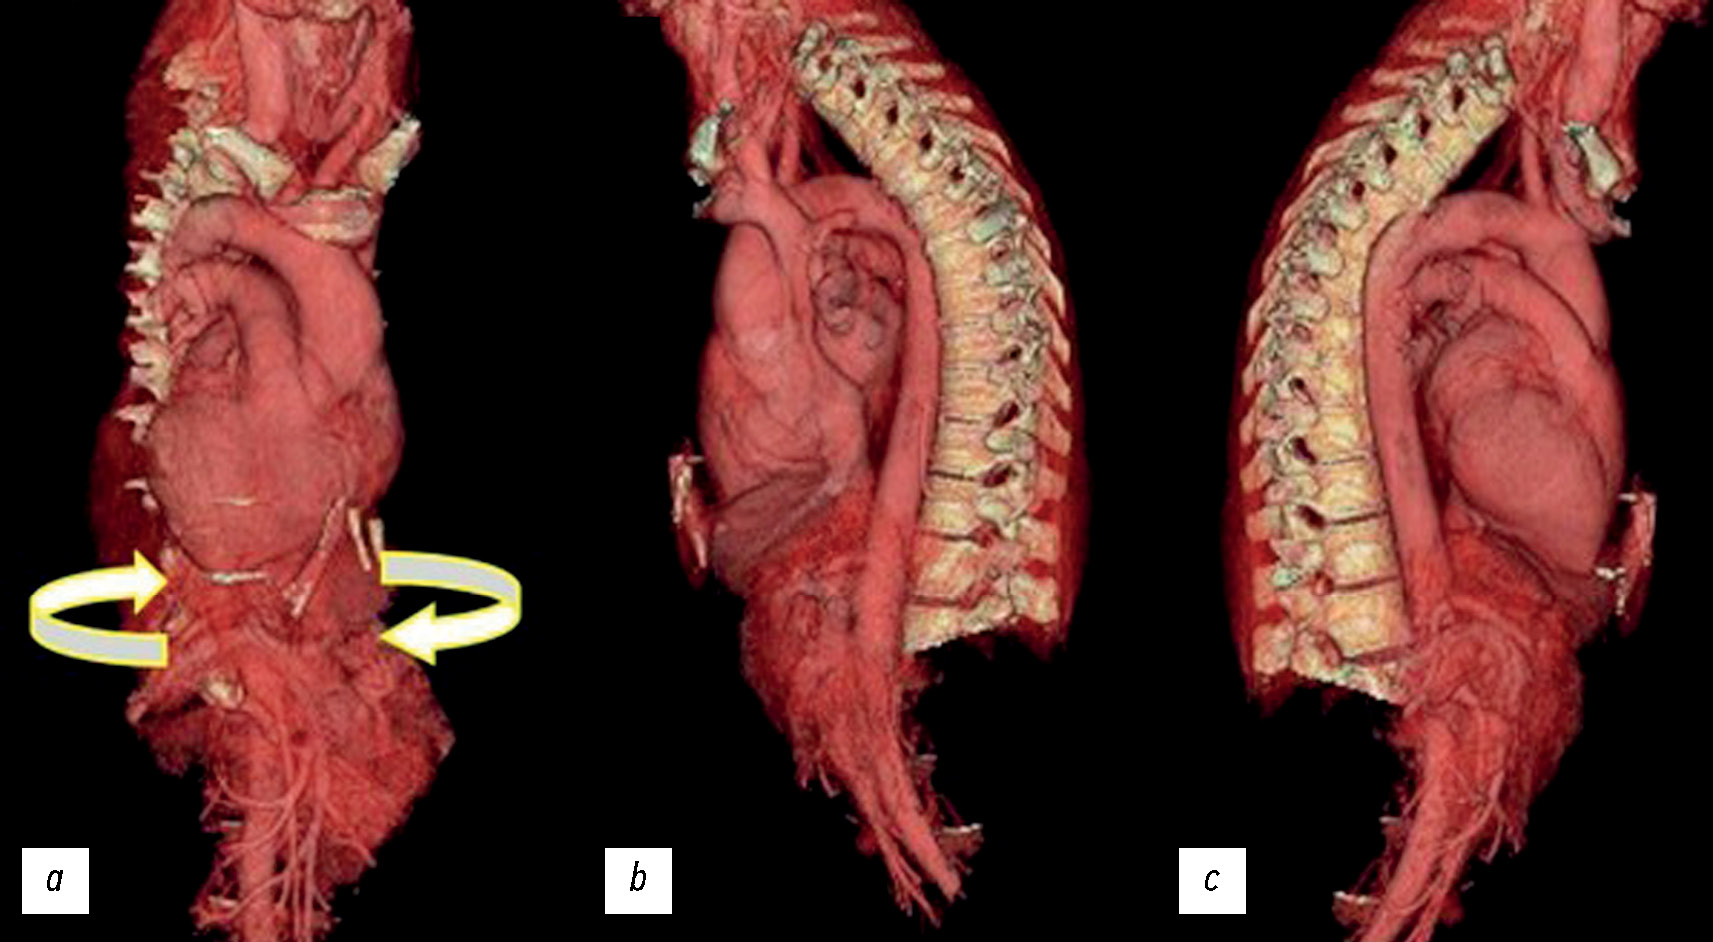

Fig. 1. Axial-computer CT images of the chest without (a) and with contrast medium (b) that show dextrocardia. In this case of situs inversus, the left lung has three lobes, the right lung has two lobes, and the heart apex is on the right.

The patient had not experienced any other significant cardiac or respiratory symptoms or previous CT. The first CT image of the thorax showed dextrocardia and a new diagnostic hypothesis was created. Further imaging studies of the thorax and abdomen confirmed the diagnosis of an unknown SIT (Fig. 2 and 3 ).